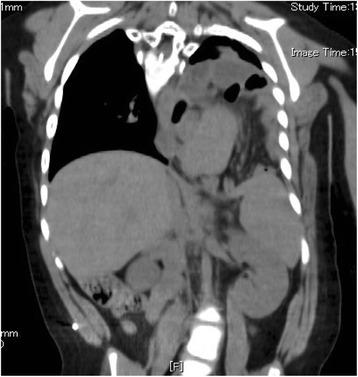

Recurrent tracheoesophageal fistula (TEF) is still difficult to diagnose and repair. In almost all cases, recurrence appears relatively soon after the primary surgery. We herein describe a case of recurrent TEF that appeared 10 years after the primary repair. At 2 years of age, the patient suffered from mental retardation due to encephalitis and developed a hiatus hernia with gastro-esophageal reflux. He underwent the repair of a hiatus hernia and fundoplication at 3 years of age. However, the hiatus hernia recurred 6 months after the operation. The patient suffered from recurrent pneumonia for 6 years after the appearance of the recurrent hiatus hernia. At 9 years of age, he was hospitalized frequently due to recurrent severe pneumonia. After admission at 9 years of age, an endoscopic study under general anesthesia was performed and revealed subglottic stenosis and a dilated esophagus with a recurrent hiatus hernia. Tracheotomy or laryngotracheal separation was first planned in order to improve his upper airway and facilitate the safer repair of the recurrent hiatus hernia. After laryngotracheal separation, the patient still suffered from severe pneumonia. In addition, a small volume of nutritional supplement was aspirated from the tracheostomy. Thus, recurrent TEF was suspected. Tests using dye under both esophagoscopy and bronchoscopy confirmed recurrent TEF. The fistula recurred in the cervical area because of the elevation of the esophagus due to the recurrent hiatus hernia. The fistula was surgically closed, with a sternothyroid muscle flap to prevent re-recurrence. At 4 months after this operation, the recurrent hiatus hernia was repaired. Thereafter, the patient's respiratory symptoms showed a dramatic improvement. The patient is now doing well and free from further recurrences of TEF and hiatus hernia at 2 years after the final operation.

复发性气管食管瘘(TEF)的诊断和修复仍然困难。几乎在所有病例中,复发都出现在初次手术后相对较短的时间内。我们在此描述一例初次修复术后10年出现的复发性TEF病例。患者2岁时因脑炎导致智力发育迟缓,并出现伴有胃食管反流的食管裂孔疝。他在3岁时接受了食管裂孔疝修补术和胃底折叠术。然而,术后6个月食管裂孔疝复发。复发性食管裂孔疝出现后,患者反复发生肺炎6年。9岁时,他因反复严重肺炎频繁住院。9岁入院后,在全身麻醉下进行了内镜检查,发现声门下狭窄和扩张的食管伴有复发性食管裂孔疝。最初计划进行气管切开术或喉气管分离术,以改善其上呼吸道并便于更安全地修复复发性食管裂孔疝。喉气管分离术后,患者仍患有严重肺炎。此外,从气管造口吸出少量营养补充剂。因此,怀疑有复发性TEF。在食管镜检查和支气管镜检查下使用染料进行的测试证实了复发性TEF。由于复发性食管裂孔疝导致食管抬高,瘘管在颈部区域复发。通过胸骨甲状肌瓣手术关闭瘘管,以防止再次复发。此次手术后4个月,修复了复发性食管裂孔疝。此后,患者的呼吸道症状有了显著改善。在最后一次手术后2年,患者目前情况良好,未再出现TEF和食管裂孔疝的复发。